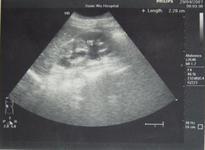

۞ 特发性腹膜后纤维化的诊断方法

۞ 特发性腹膜后纤维化的辅助检查